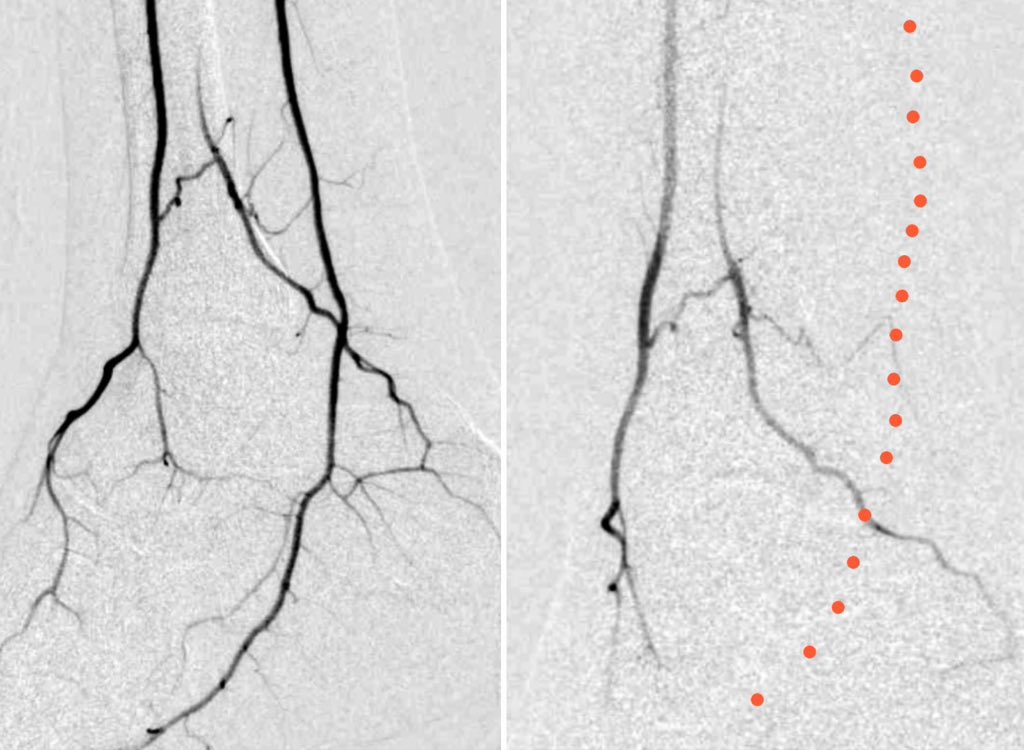

في رحاب منى، جمعتني هذه الصورة بأخي الذي ولدته لي الأيام HaniBadahdah, MD تعاهدنا أن نكون صوتاً و احداً في التوعية، وعملاً مستمراً لمحاربة #البتر رسالتنا الوقاية أولاً، والعلاج مبكراً ، والبتر ليس حتمياً #القدم_السكرية #وعي_وحياة #حج_1446 #حج_بصحة